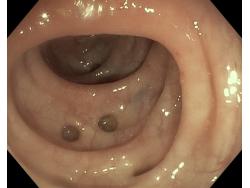

Uchyłki